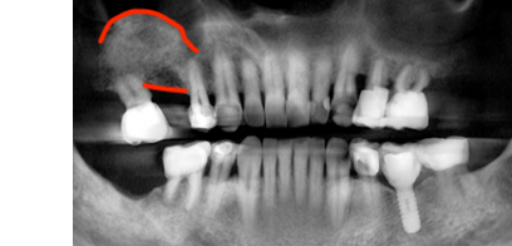

Comparison of dental before and after photos, showing improved implant health after LAPIP.

Laser Assisted Peri-implantitis Procedure

(To treat peri-implant disease)